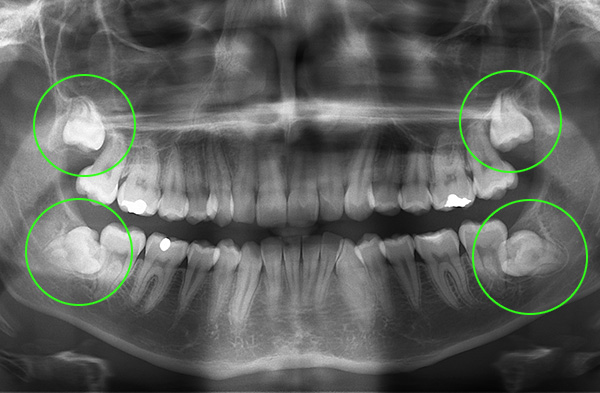

Nella radiografia in basso, i denti permanenti nell'osso, formati sotto il latte e pronti a spingerli, sono chiaramente visibili:

In ogni caso, solo il dentista può capire il motivo del ritardo nella sostituzione dei denti temporanei dopo l'esame: verrà eseguita una radiografia. Dopo aver valutato l'immagine, l'ortodontista discute le opzioni di trattamento.